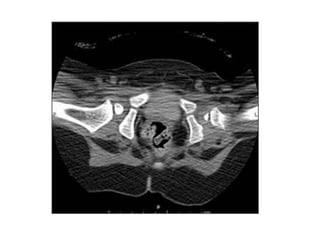

MRG, BT

•   Anestezi gereksinimi

•   Tek pozisyonda statik görüntü

•   Tedavide yol gösterici değil

•   Radyasyon

MRG, BT • Anestezi gereksinimi • Tek pozisyonda statik görüntü • Tedavide yol gösterici değil • Radyasyon